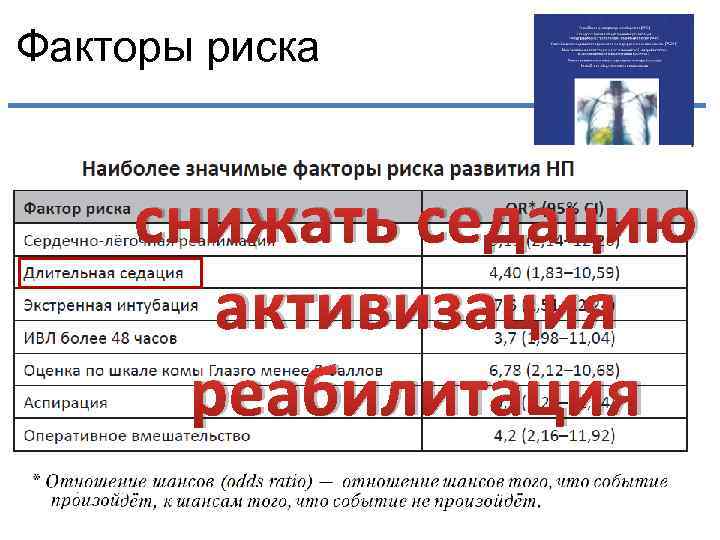

Факторы риска снижать седацию активизация реабилитация

Факторы риска снижать седацию активизация реабилитация